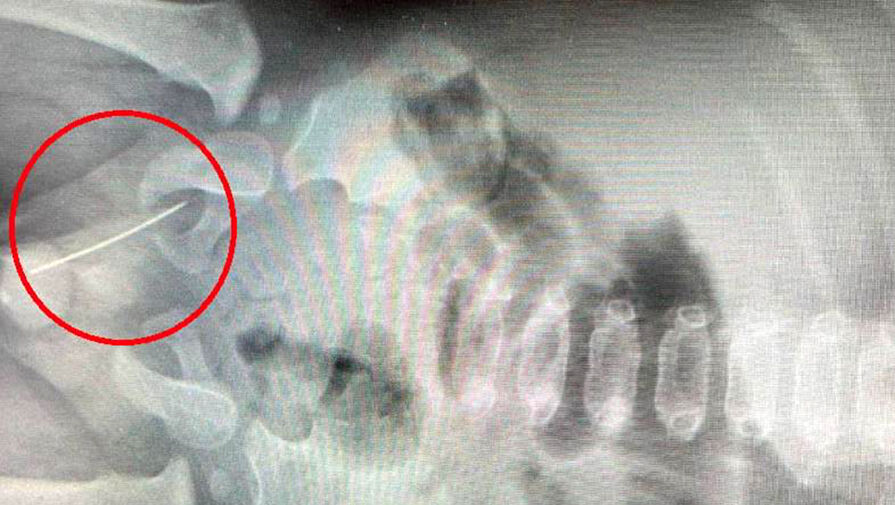

Ребенок был доставлен в больницу бригадой скорой помощи с сильной болью, не позволявшей ему встать. В ходе обследования медики обнаружили в мягких тканях между мошонкой и прямой кишкой швейную иглу, прошедшую в непосредственной близости от уретры.